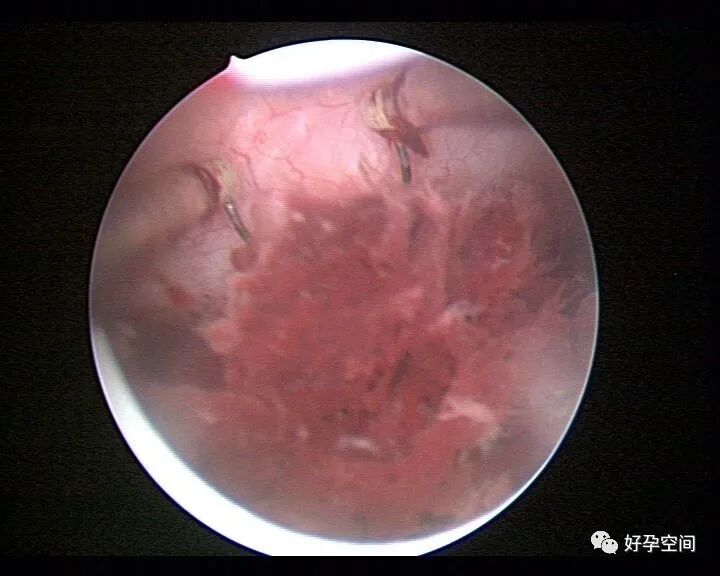

病例3:(病人年龄及取卵个数不详)取卵术后血尿膀胱内血块尿潴留,膀胱灌洗效果不佳,宫腔镜探查膀胱,清除血块,膀胱多处穿刺伤,电凝止血。

病例4:32岁,取卵13枚,取卵术后血尿膀胱内血块尿潴留,膀胱灌洗效果不佳,宫腔镜探查膀胱,清除血块,膀胱底见穿刺伤,电凝止血。